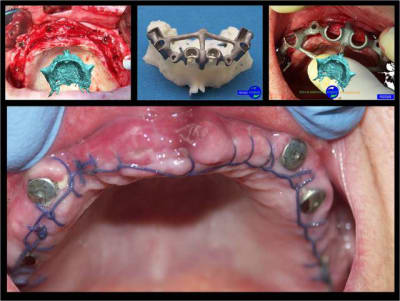

votre avis sur ce cas clinique

suite

précision de la chirurgie guidée condensée

Le guide chirurgical, positionneur d’implants reste en place jusqu’à la pose des implants.

cicatrisation gingivale, suite expansion